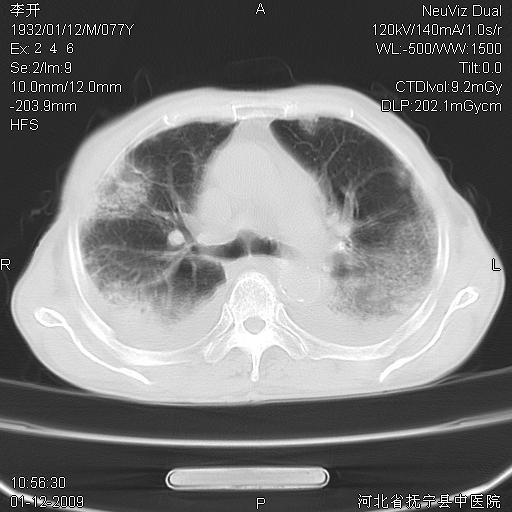

以下是引用黑白光影在2009-1-19 16:49:00的发言:[br]心衰肺水肿;心包、胸腔积液;冠脉钙化;肺部感染。